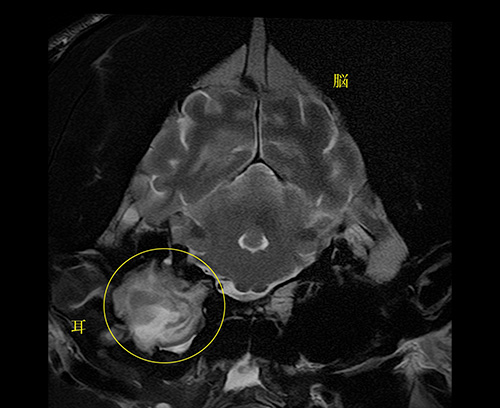

脳腫瘍